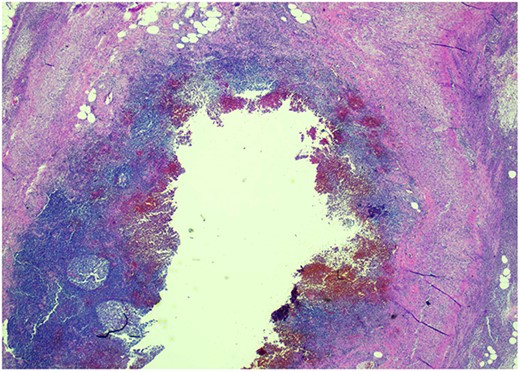

Pathology resulted on post-operative day three showing an inflamed appendix, 1.4 cm in diameter, with an exudative-filled lumen. On microscopic stains, there was evidence of acute appendicitis with frequent scattered unicellular organisms within areas of ulcerated appendiceal mucosa and submucosa (Figs 6 and 7). These cellular forms have round cell membranes, single prominent round eosinophilic nuclei and foamy cytoplasm (Fig. 5). Occasional forms show evidence of erythrophagocytosis (Fig. 3). Forms were also highlighted by trichrome and PAS special stains (block A1) and were negative for CD68 (a marker of macrophages; block A1) (Figs 2–4). These morphologic features are most consistent with E. histolytica, which is a pathogenic parasite in the lower GI tract, and likely the causative agent for acute appendicitis in this case.

Trichrome stain—parasites are positive; erythrophagocytosis supporting Entamoeba histolytica.